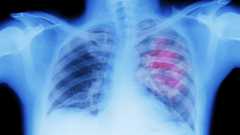

Cancer patients are much less protected against Covid-19 than other people after one dose of the Pfizer vaccine, the first real-world study in this area suggests.

Researchers at King's College London and Francis Crick Institute warn that a 12-week wait for the second dose could leave them vulnerable.

An early second dose appeared to boost cancer patients' protection.

Cancer charities are calling for the current UK vaccine strategy to be reviewed.

But Cancer Research UK added that the small study had not yet been reviewed by other scientists and people undergoing cancer treatment should continue to follow the advice of their doctors.